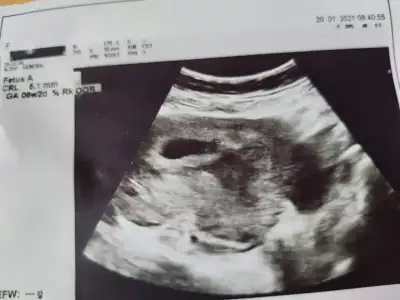

Ben de bugün kalp atışını duymadım ama gördüm pitpit benim hesabıma göre 6+5 ama doktor 6+2 dedi. Sormadım niye diye. Bir de dandik bir ultrason görüntumuz var, sol tarafta sağa yaslı gibi duruyor. Tahminen ne oluyor